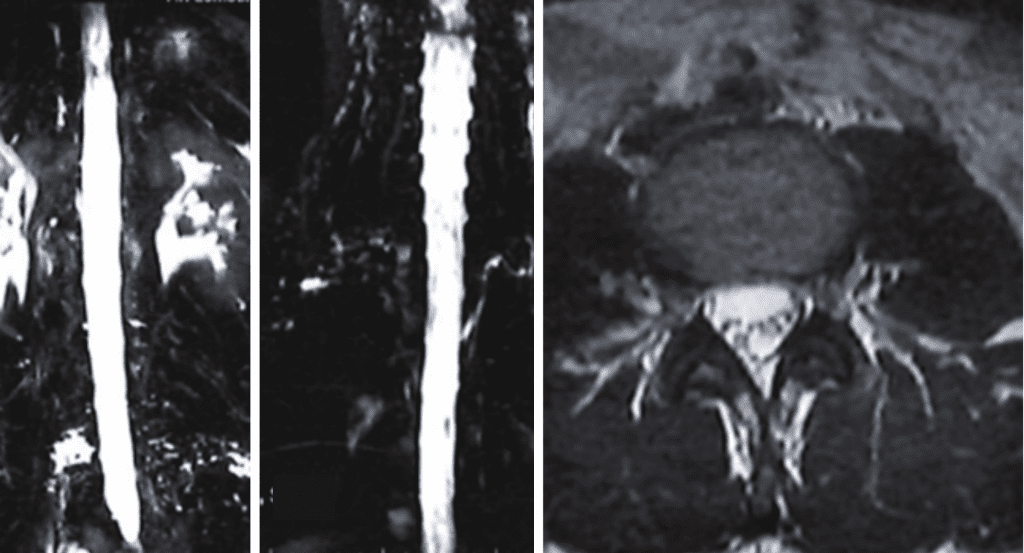

Fig 2. MRI of thoracic spine showing syringomyelia.

As in her case, MRI imaging, with heavily weighted T2 Fat-Saturated Sequences (3D-T2WI-FS) provide a very high accuracy for the CSF leak presence into the epidural space. Multiple imaging sites are usually identified, although at surgery or with dynamic CT myelography, only one site is found.

Imaging and other provocative diagnostic test showed the associated problems of Cranial Cervical Instability, incidental thoracic syringomyelia, Hashimoto Thyroidistis, Polycystic Ovarian Syndrome, Nutcracker Syndrome, Postural Orthostatic Hypotension, and Hypo/Hyper intracranial Pressure with spontaneous CSF leaks.